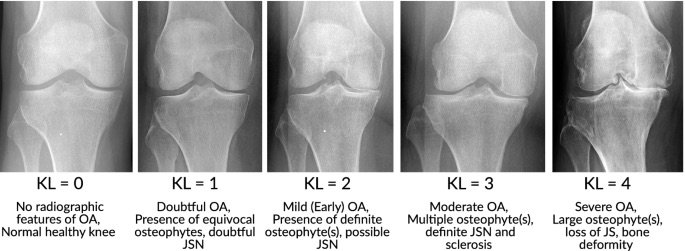

Radiologically X-rays show the progress of Osteoarthritis through 4 stages.

Treatment of Osteoarthritis is based on the stage of knee arthritis and hence X-rays play an important role in management of Osteoarthritis